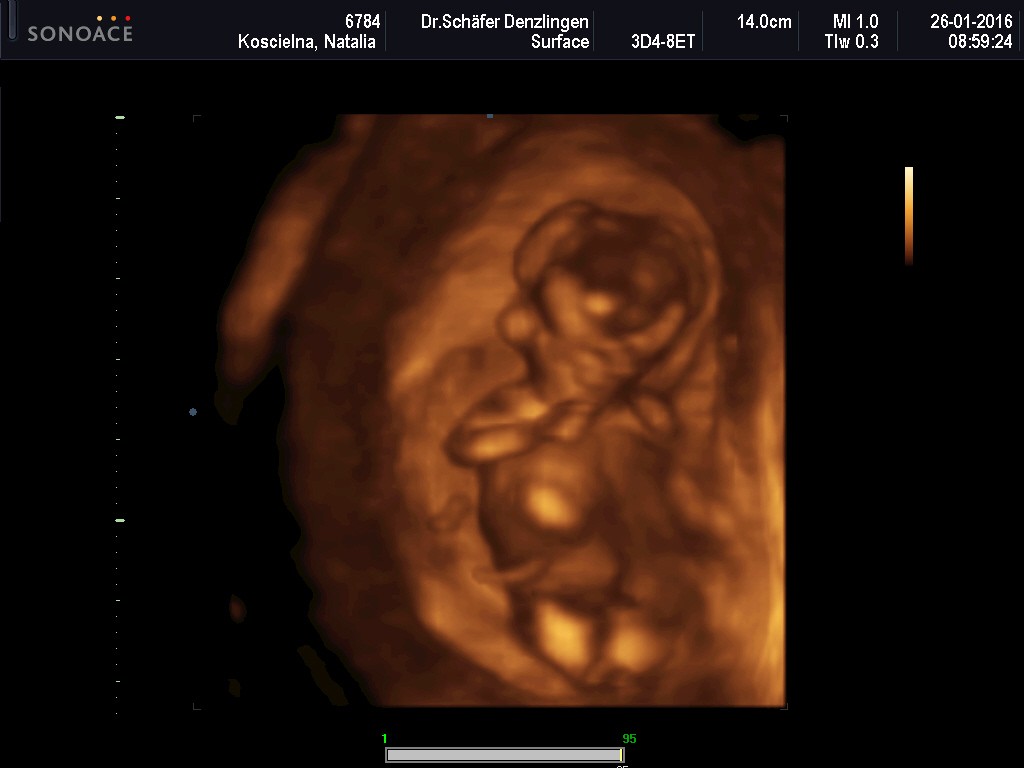

Wczoraj miałam wizytę - wszystko ok, ciąża troszkę większa, bo wszytskie pomiary pokazywały na 12+4, wszystko ok, więc ulga wielka, bardzo długo mi robił usg, mierzył i wszystko ok. Kolejne badania do zrobienia na tokspolazmoze a już sama chciałam sobie robić. Kolejna wizyta za 3 tygodnie. pokazuje zdjęcie z usg, po lewejrączka przy główce, na drugim nóżki i brzuszek![]()

dał mi zdjęcie i mówi :ma Pani swoje nóżki i rączki